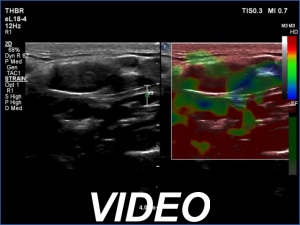

Ultrasonography revealed hypoechoic discrete lesions in both thyroid lobes. The lesions presented microcalcifications. Corresponding to the palpable mass in the right submandibular region, a reactive-type regular lymph node was found. There was an enlarged lymph node in the left submandibular region. The node had a regular hilum but displayed a heterogeneous pattern.

Cytology was performed from both lymph nodes and from the lesion in the left thyroid bed. FNA resulted in non-diagnostic report from the lesion in the left thyroid bed while cytology of the submandibular lymph nodes showed patterns of a benign, reactive-type lymph node.

Wash-out thyroglobulin levels were 0, 81.1 and 104.9 ng/mL, right submandibular lymph node, left thyroid bed lesion and left submandibular lymph node, respectively.

Comment. Until the final histological examination is completed, I would like to draw attention to two things. One is the heterogeneity of the left lymph node and the other is the size and structure of the lesions in the thyroid beds - these features are suspicious of thyroid cancer.